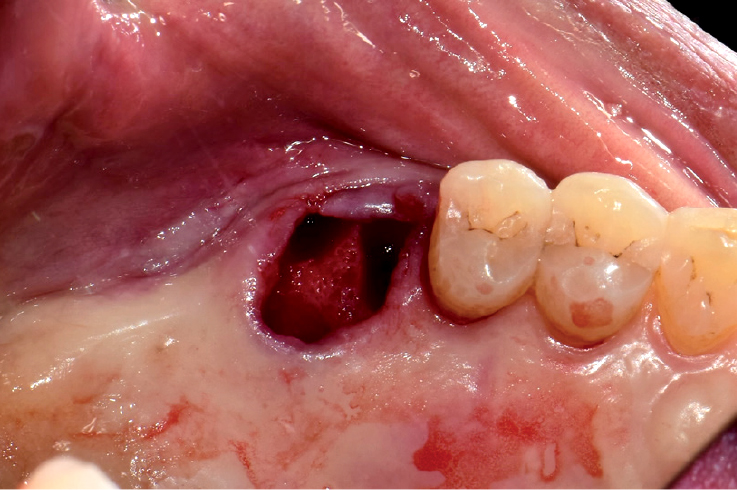

EASY EXTRACTION BASIC KIT IS USEFUL FOR THE FOLLOWING CASES

- Immediate implant placement following extraction

Before

After